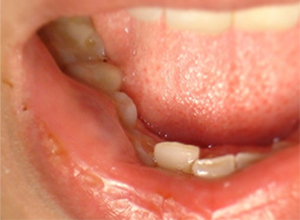

• Mucocele de labio inferior

Mucoceles

Es la acumulación de saliva dentro de una cavidad quística.

Hay dos tipos de mucocele de extravasación y de retención.

El 70% de los quistes de extravasación se observan en el labio inferior.